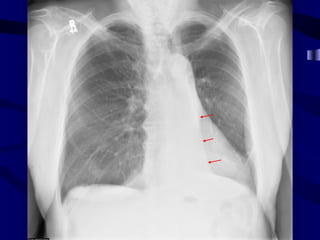

Paratracheal ln

Right Paratracheal Lymphadenopathy